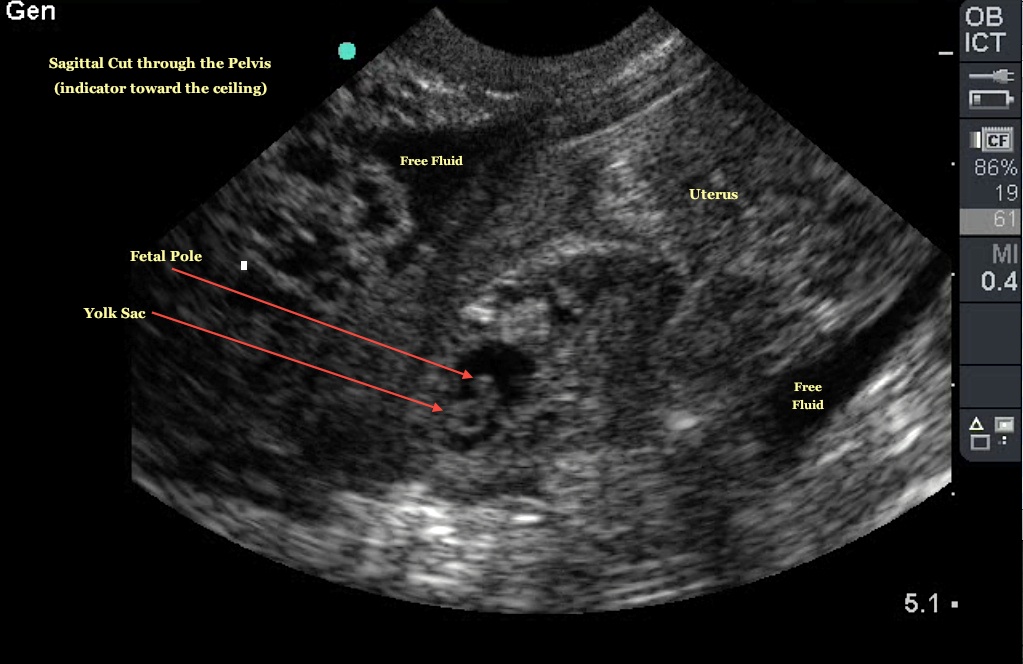

عکس سونوگرافی بارداری خارج از رحم